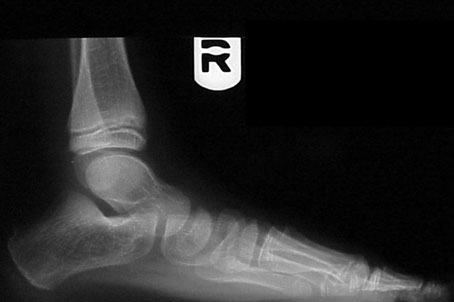

Sagittal plane deformities. A line bisecting the talus on the lateral radiograph should continue distally and downward so it parallels the first metatarsal shaft. If it does this, the navicular and the first cuneiform are presumably in line as well. If it does not, then there is sagittal failure somewhere along the medial column.

This failure can occur at the talonavicular joint, the cuneonavicular joint, the first metatarsocuneiform joint or in several of these areas at the same time. This failure results in the familiar “fault.” When this occurs, the talus goes into obligatory plantarflexion and the ankle goes into some degree of equinus position. The result is a plantigrade medial side of the foot. The sagittal failure can be flexible or rigid. When it is flexible, it is referred to as forefoot supinatus. When it is rigid, it becomes irreducible forefoot varus. The effect on subtalar range of motion varies from case to case but generally requires subtalar pronation to get the medial column down to the weightbearing surface.

Radiographs show a very wide AP talocalcaneal angle with an abducted forefoot. The lateral view shows sagittal instability of the medial column. The deformity is most pronounced on the transverse plane.

Standing AP radiographs show the AP talocalcaneal angle is preserved. The lateral radiograph shows marked medial column collapse.

Presumably, the patient is fully pronated in stance and gait. Pain is limited to the talonavicular, calcaneocuboid and sinus tarsi areas. The therapeutic goals are control of the excess pronation and accommodation of the forefoot varus. The deformity dominates in the sagittal plane. Its rigidity limits orthotic therapy to support. One can try a partially pronated device with accommodation for part of the forefoot varus. Physicians should also consider surgical options.